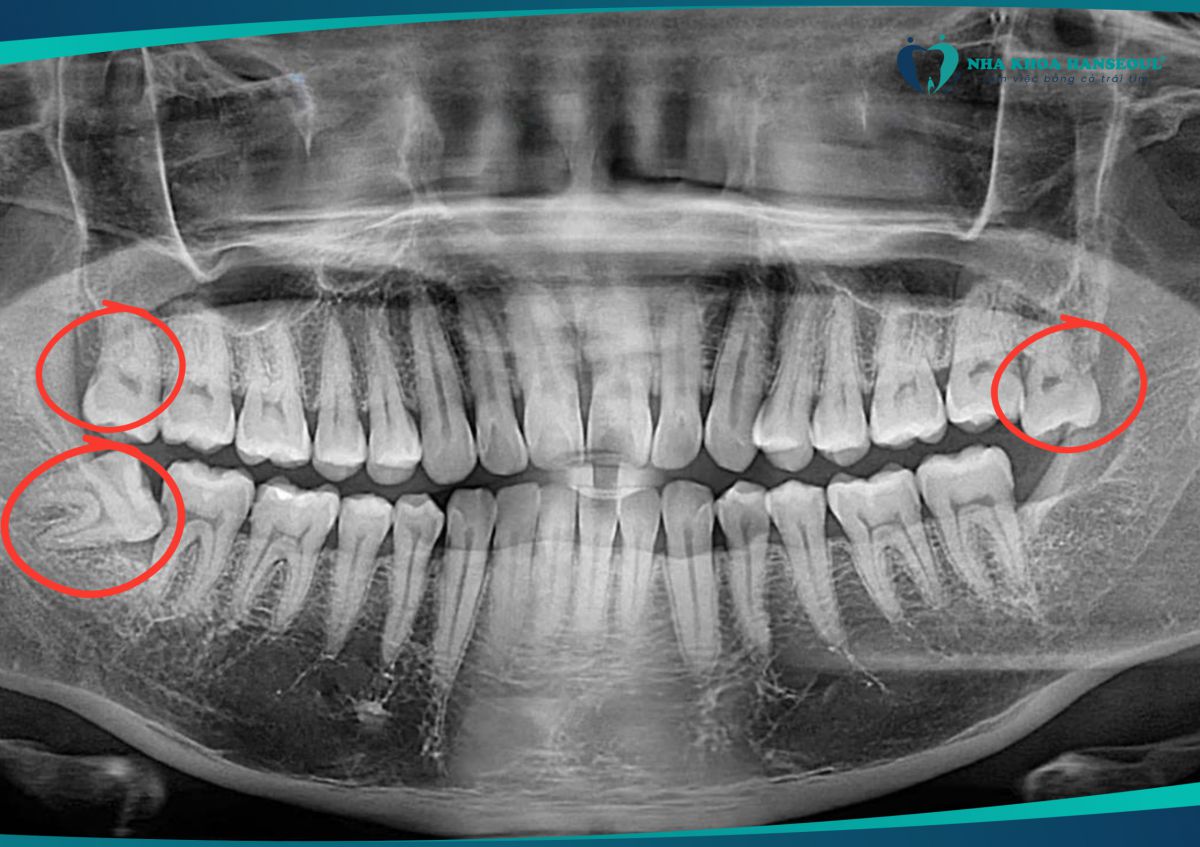

Khi đến Nha khoa Hanseoul, anh Lành gặp phải tình trạng:

- Răng khôn hàm dưới mọc nghiêng 60 độ, gây tiêu xương, sâu răng số 7 và có nguy cơ lung lay răng hàm quan trọng.

- 2 răng khôn hàm trên mọc thẳng nhưng thòng xuống, khiến thức ăn dắt vào kẽ răng, tạo điều kiện viêm nhiễm.

Nếu không xử lý kịp thời, những chiếc răng này sẽ ảnh hưởng nghiêm trọng đến sức khỏe răng miệng. Sau khi thăm khám kỹ lưỡng, Ths. Bs Trần Việt Hà (Nha khoa Hanseoul) đã chỉ định nhổ cả 3 răng cùng lúc để giải quyết triệt để vấn đề.

Tình trạng răng khôn của anh Lành trước khi điều trị